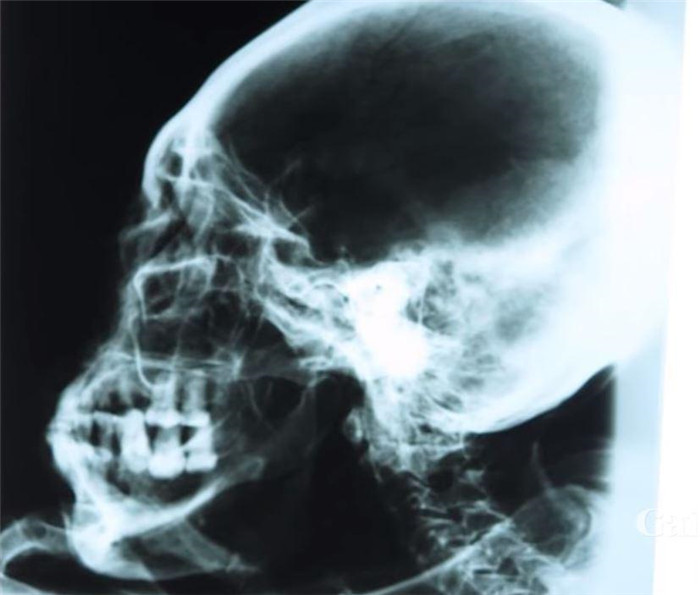

▼頭骨和指頭的X射線显示,干屍是真實的。